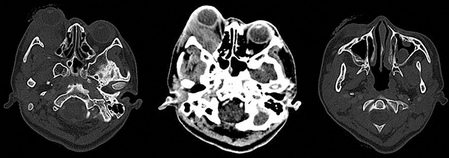

La ultrasonografía ocular reportó una lesión heterogénea que ejercía compresión y desplazamiento en sentido anterior del globo ocular derecho, y datos de inflamación de tejidos blandos (Figura 1). La tomografía computada describió la lesión como heterogénea e identificó datos de sinusitis y proptosis (Figura 2). Por resonancia magnética se reportó la misma lesión con aspecto heterogéneo de 5.5 ' 2.5 cm en sus diámetros mayores, que involucró tejidos musculares y con efecto de masa sobre estructuras orbitarias. No se observó extensión intracraneal, a cavidades paranasales ni al seno cavernoso (Figura 3). Ante una proptosis de rápida evolución y sospecha de probable rabdomiosarcoma se realizó biopsia transconjuntival de lesión intraconal y tejido peri-orbitario. Las preparaciones histológicas de la lesión intraconal y de la grasa orbitaria mostraron tejidos blandos con un proceso inflamatorio, necrótico con vasculitis de vasos de pequeño calibre con afección ocasional a vasos arteriales y venosos de mayor calibre. La vasculitis fue a expensas de linfocitos e histiocitos con trombosis aislada y algunos granulomas mal constituidos. El proceso inflamatorio estaba constituido por linfocitos, histiocitos, células plasmáticas y en una zona se mezclan con numerosos neutrófilos con cariorexis; la necrosis fue isquémica. Se realizaron diversas tinciones de histoquímica convencional e inmunohistoquímica para descartar neoplasia linfoide maligna o proceso infeccioso granulomatoso como micobacterias u hongos. La glándula lagrimal mostró afección por el proceso inflamatorio, la necrosis isquémica y la propia vasculitis. El diagnóstico fue de: granulomatosis de Wegener (Figura 4).

Figura 2 Tomografía axial computada. Se observa lesión lobulada de bordes mal delimitados en región superolateral de la órbita, de 53 × 23 × 38 mm en sus ejes anteroposterior, transverso y craneocaudal, respectivamente. Reforzamiento heterogéneo, en promedio de 50 UH, con componente intra- y extraconal lateral. Pobre interfase entre la lesión nervio óptico ipsilateral, así como con el músculo recto inferior. Las paredes de la órbita se encontraron respetadas, sin alteraciones en fosas temporales. Incremento de la densidad de los tejidos blandos palpebrales tanto superiores como inferiores, engrosamiento mucoso en senos maxilares y esfenoidal izquierdo con presencia de imágenes polipoideas, de hasta 50 UH. UH: unidades Hunsfield.